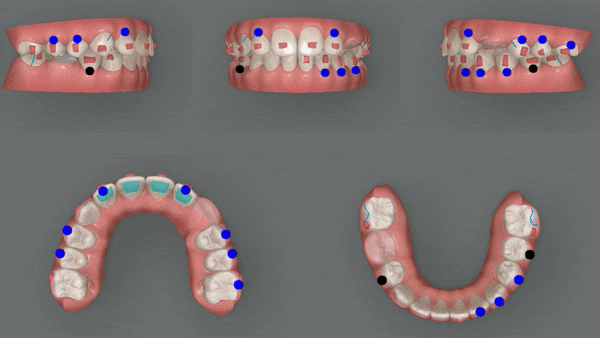

2nd(30개)

치아배열이 어느정도 완성이 되었으나

두번째 클린체크 에서는

이전의 클린체크를 보완해 교정치료의 완성도를 높여 줍니다.

첫번째 클린체크에서는 치아의 배열에 중점을 두었다면

두번째 클린체크에서는 위와 아랫니의 교합을 정돈하기 위한 치료를

진행해드렸습니다 ^^

3rd(25개)

인비절라인의 또 다른 장점 중 하나는

악궁 확장에 상당히 효과적인 기능을 가지고 있습니다.

공간이 부족하면 발치교정을 해야 했던 이전과는 달리

특수강화 플라스틱 재질인 인비절라인은

치아를 안쪽과 바깥쪽에서 적은 힘으로 지속적으로 잡아주기 때문에

거의 통증없이 악궁을 확장시켜 치아이동에 관여합니다.

4th(14개)

마지막으로 섬세한 디테일링을 위해

네번째 클린체크

(총 14개의 장치)를 진행해드렸습니다.

이전의 클린체크와는 어태치먼트의 모양과 위치가

달라져